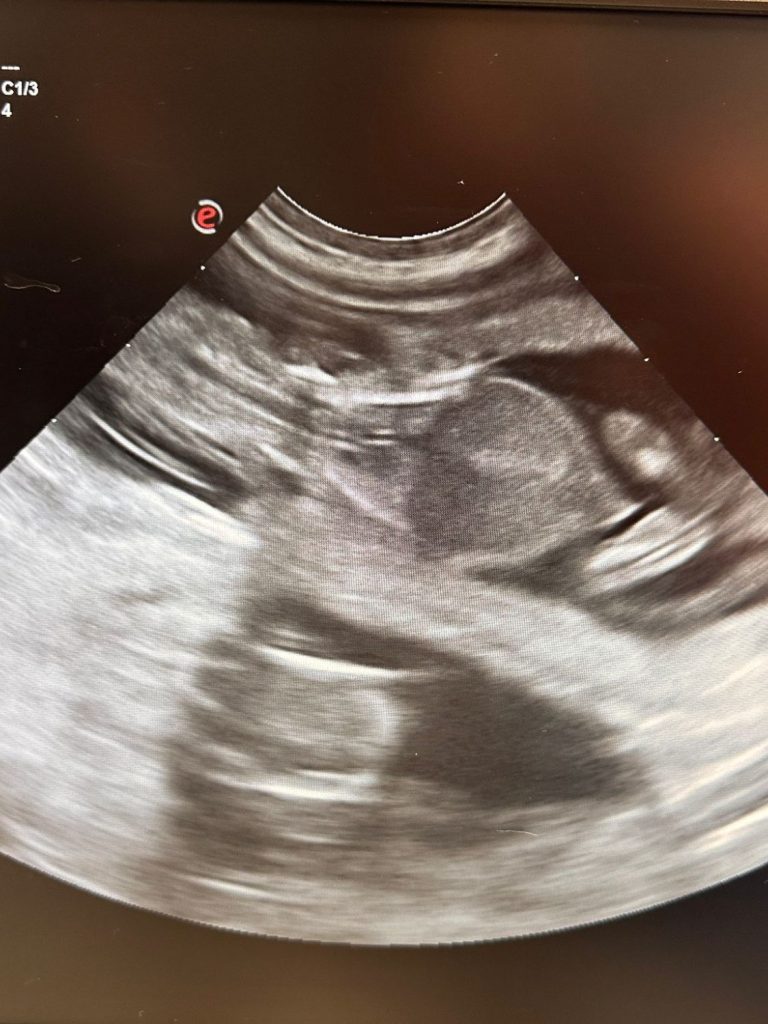

Freudige Nachricht: Ælla ist wieder trächtig! Die sonographische Untersuchung konnte zeigen, dass die Verpaarung geklappt hat und es konnten 3 Welpen gleichzeitig dargestellt werden. Es werden aber mit etwas mehr Welpen gerechnet. Ab Trächtigkeitstag 55 wird für die Gewissheit, dass alle Welpen bei der Geburt ausgetrieben werden, ein Röntgen vom Abdomen erstellt um die kleinen Skelette zu zählen. Wir freuen uns, dass sich der Aufwand, den wir bis dahin schon betrieben haben, gelohnt hat!